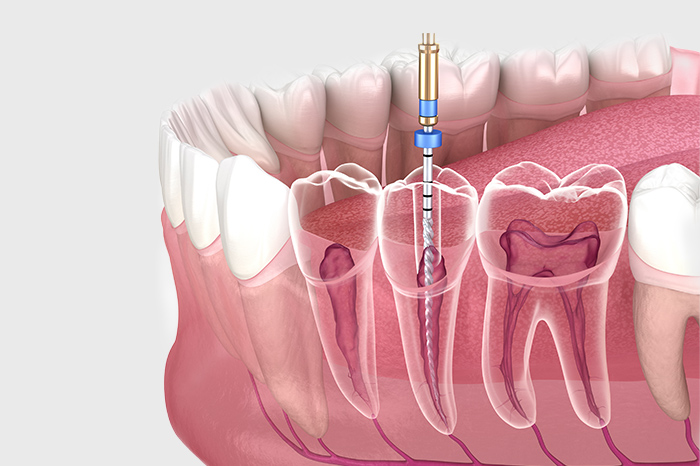

根管治療について

進行してしまったむし歯には

根管治療で対応いたします

むし歯が進行して歯内部の歯髄まで進行してしまった場合、一般的なむし歯治療では対処できません。歯の根の治療である根管治療を実施して、歯内部の感染部分を除去する必要があります。根管治療を行うことで、抜歯の検討が必要なほど進行したむし歯でも、歯を残せる可能性があります。

Nitiファイル

感染部分を除去する際、ニッケルチタン製のファイルを使用します。柔軟性が高いため、複雑な根管内でも処置しやすい器具です。

根管拡大装置(Xスマート)

根管形成を目的とする機器であり、ファイルを回転させることで正確に根管拡大・形成していきます。精度の高い治療に必要な設備です。